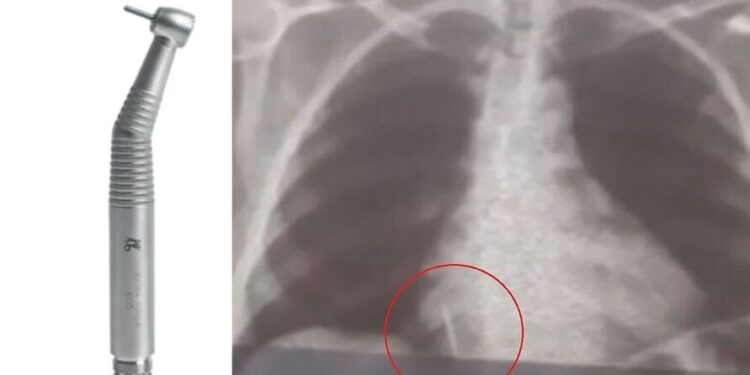

Iolanda Mariano de Melo Simplício está com o material alojado no pulmão deste então. O filho dela conta que a mãe sente muitas dores e já perdeu cerca de 10 quilos desde o ocorrido.

“A principal causa é a não adaptação entre a caneta de alta rotação, que é o motor que o cirurgião dentista utiliza na realização de procedimentos odontológicos, com a broca. A partir dessa não adaptação, é possível o paciente acidentalmente broncoaspirar esse instrumento”, falou.